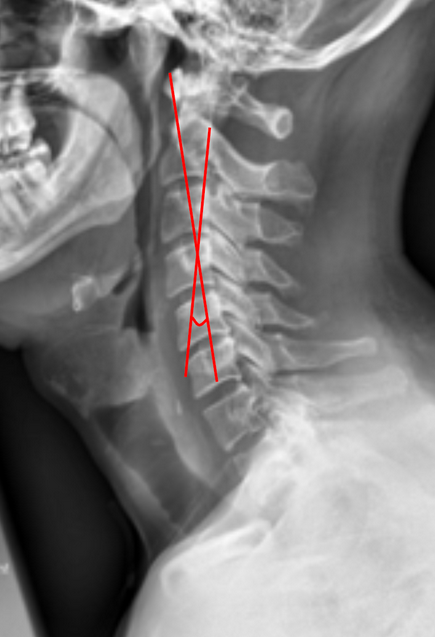

C2 Tilt quantifies the inclination of the axis (C2 vertebra) relative to the vertical axis of the cervical spine and a line drawn parallel to the posterior cortex of the odontoid and is an important parameter for assessing cervical sagittal alignment.

2) Instructions to Measure

• Obtain a neutral, standing lateral cervical spine X-ray

• Identify the inferior endplate of C2

• Draw a horizontal line along the inferior endplate of C2

• Draw a true vertical reference line perpendicular to the inferior endplate

• Draw a line parallel to the posterior cortex of the odontoid

• Measure the angle between the reference line and the posterior odontoid line